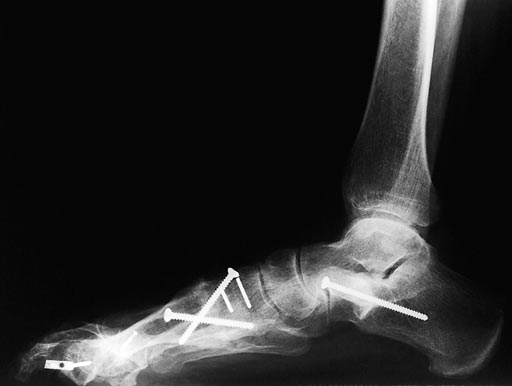

Correction of malunited Akin osteotomy D1 and shortening of the middle phalanx D2 of a flexible hammer toe using a Locking Two-Hole Plate for each correction.